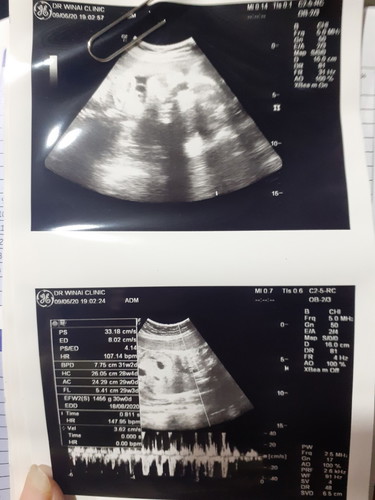

หญิงหรือชายค่ะ

ช่วยดูให้หน่อยได้มั้ยค่ะ

ดูไม่ออกเลยค่ะแม่ ว่าเป็นส่วนไหน หมอว่ายังไงบ้างคะ

ดูไม่ออกเลยจ้า ไม่ชัดเลย

ไม่ชัดค่ะ ดูไม่ออก

ดูไม่ออกเลยค่ะแม่